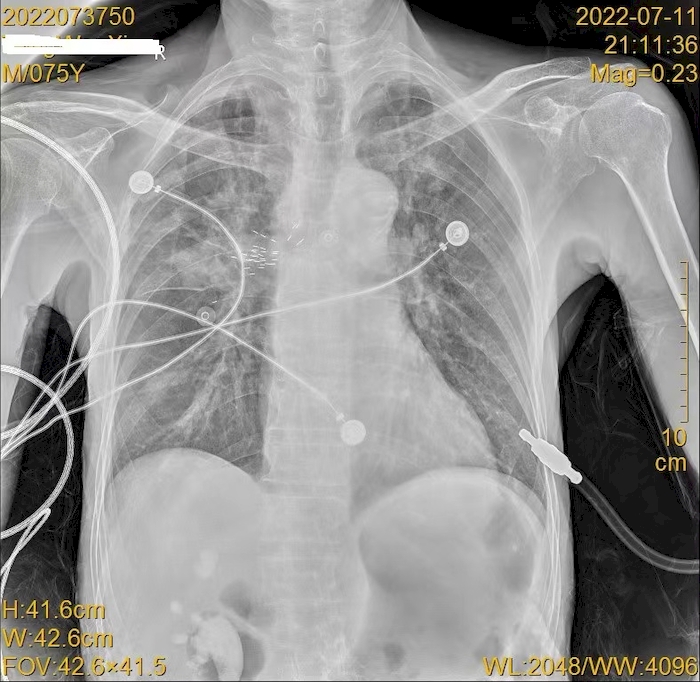

放射性粒子植入术后复查胸片查看粒子位置。于涛供图

经过详细准备,7月11日,在麻醉科及内镜中心团队大力支持和配合下,呼吸内科副主任医师李文利、于涛成功为汤先生实施了全麻下经超声支气管镜下放射性粒子植入术。即在麻醉成功后经喉罩进镜,经依靠超声支气管镜定位病灶,测量病灶大小,做好术中手术规划,在超声支气管镜引导下穿刺植入放射性粒子(碘125)36粒,手术顺利,术后患者安返病房,并于术后第二天出院。